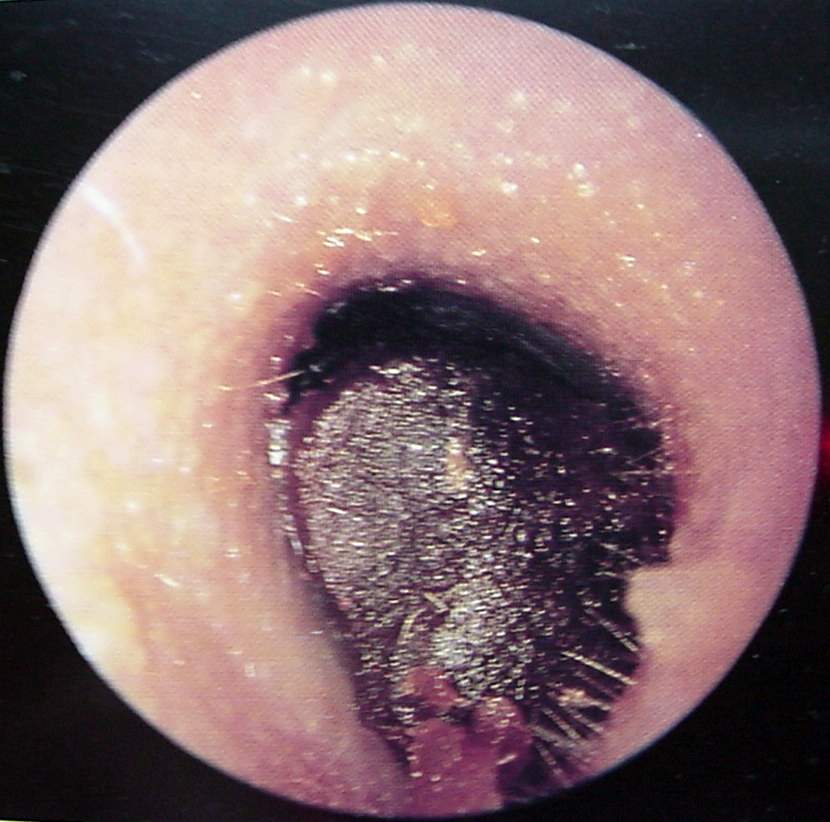

Ear Clinical Photos for Static Stations